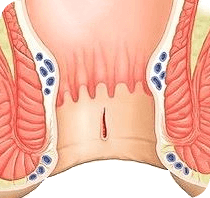

La cosa principale del problema delle emorroidi è che in nessun

caso dovrebbe essere trascurato. Non appena compaiono i primi

sintomi, è necessario iniziare a combattere il problema. Lo

stile di vita e la nutrizione sono importanti, ma se i sintomi

delle emorroidi sono già comparsi, solo queste misure non

aiuteranno. Se non ti accorgi in tempo, purtroppo, solo la